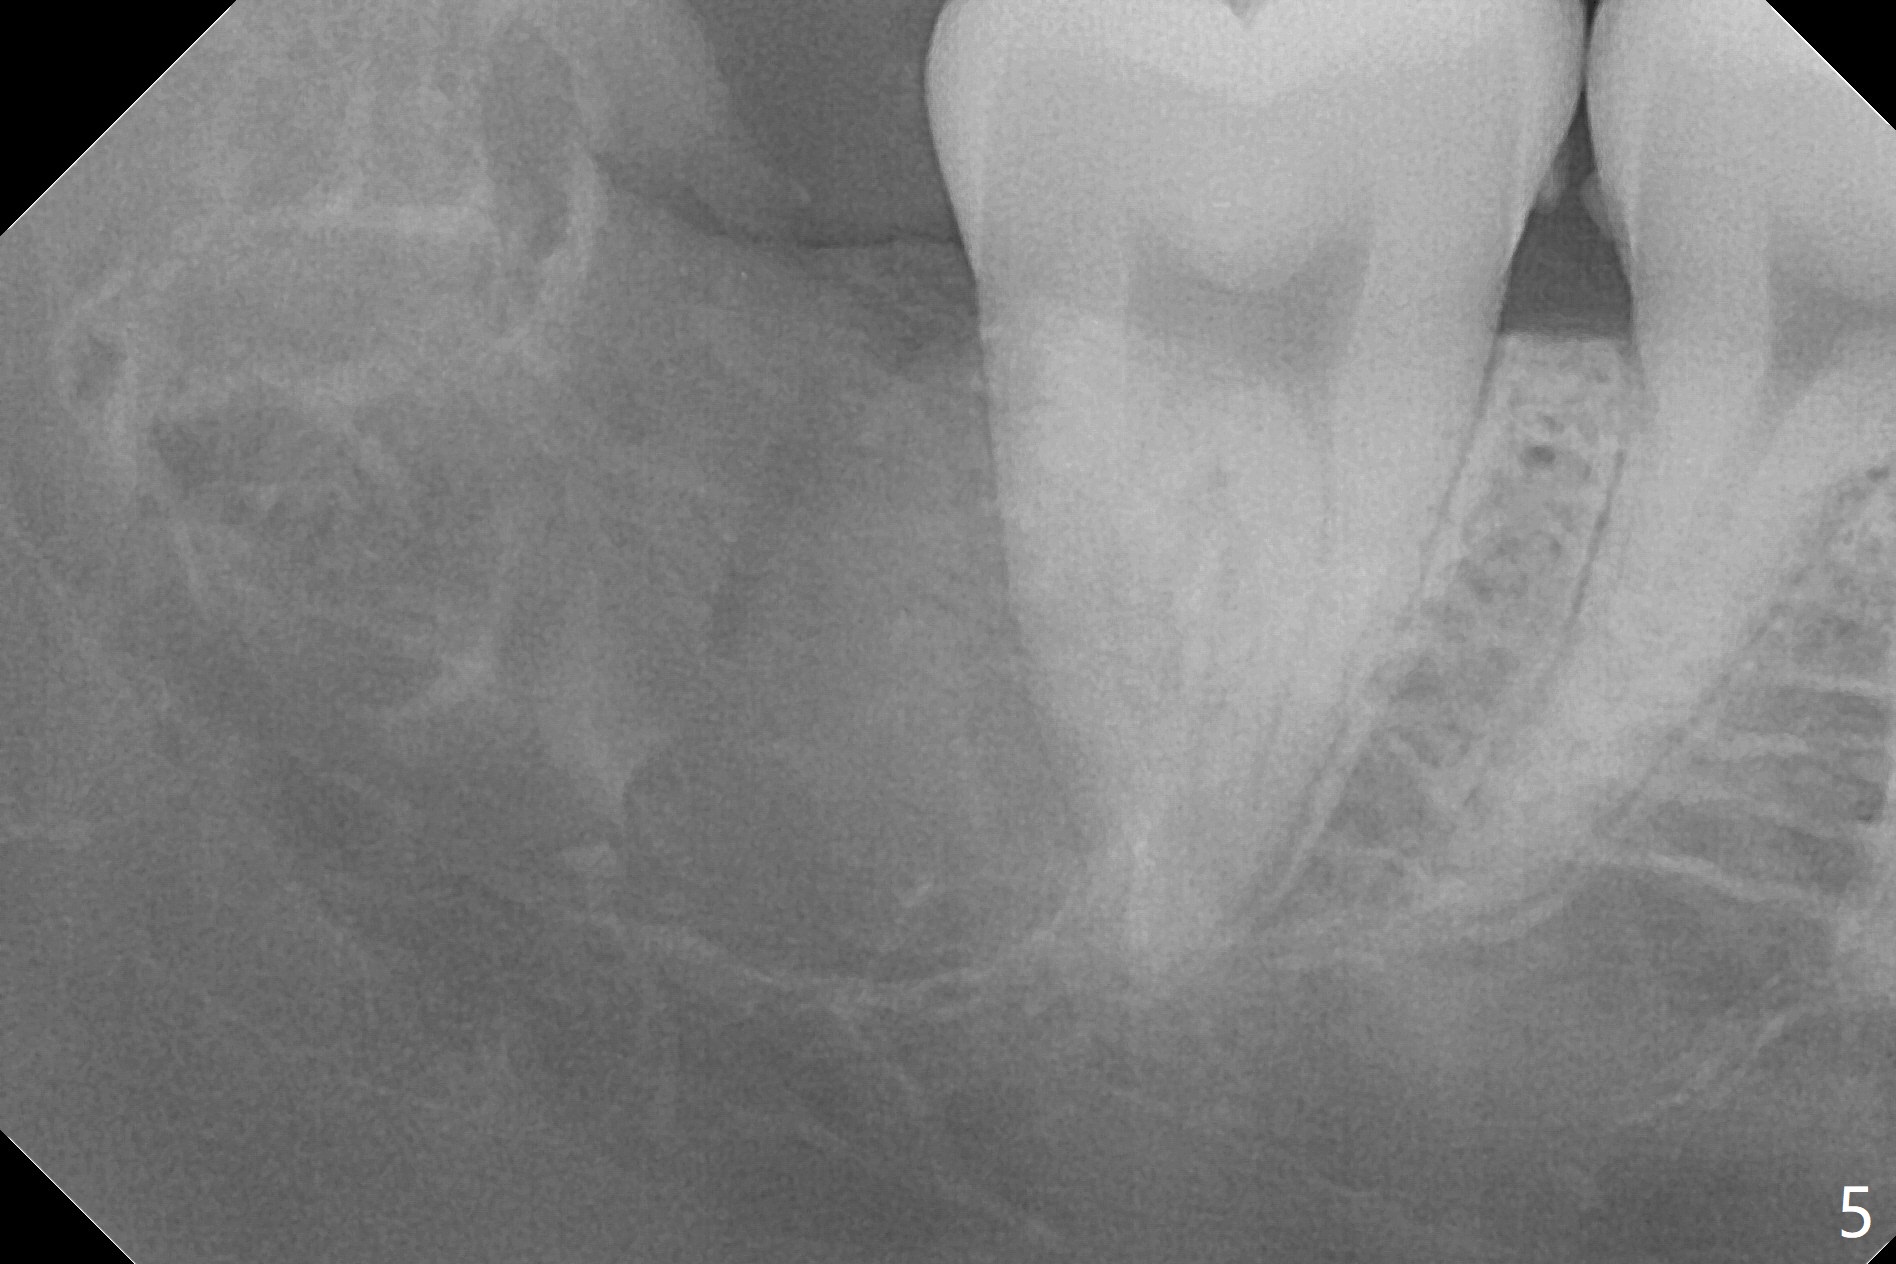

A 17-year-old man will return for extraction of 4 of the 3rd molars (Fig.1). Since the distobuccal surface of the tooth #31 may lack the bone (Fig.2 *), half of Augma will be placed in the distal portion of the sockets of #17 and 32, while allograft in the mesial one. Take PAs immediately post extraction to determine bony defects of the lower 3rd molars. Insert a piece of 2x2 gauze into the socket immediately post extraction. If hemorrhage is severe because of closeness between the mesial roots of the lower 3rd molars and the Inferior Alveolar Canal (Fig.2,3 red dashed line) after removal of the gauze, insert a half piece of Collagen Plug or more into the socket. If the latter is effective in hemostasis, Augma will be not applied, but allograft will be used, followed by Collagen Plug on the top of the allograft and sutures. Prepare both 4-0 and 5-0 ones. In fact the patient chooses to have 2 of the 3rd molars to be extracted. The extraction at #32 turns out to be extremely difficult with numerous sectioning because the crown of #32 is embedded into the distolingual surface of the fused conical roots of #31 (Fig.4,5). After insertion of a whole piece of Osteogen plug (Fig.7 O) into the root portion of the socket, Bond Apatite (1 cc) is pressed into the coronal portion of the socket (Fig.6 A). Due to oozing, the cement does not seem to be set completely. One third piece of Collagen plug is placed on the top of the cement before 4-0 Chromic gut suturing tightly. CBCT will be taken for better treatment approach prior to #17 extraction. Return to Plug Augma Xin Wei, DDS, PhD, MS 1st edition 10/06/2019, last revision 12/28/2019